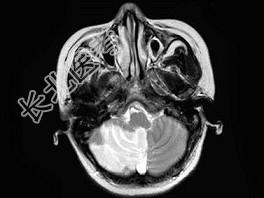

- 单项选择题女,58岁, 突发走路不稳1天,MRI检查见右小脑半球异常信号, 最可能的诊断为 ( )

A、脑梗死

B、病毒性脑炎

C、脑出血

D、星形细胞瘤

E、未见异常